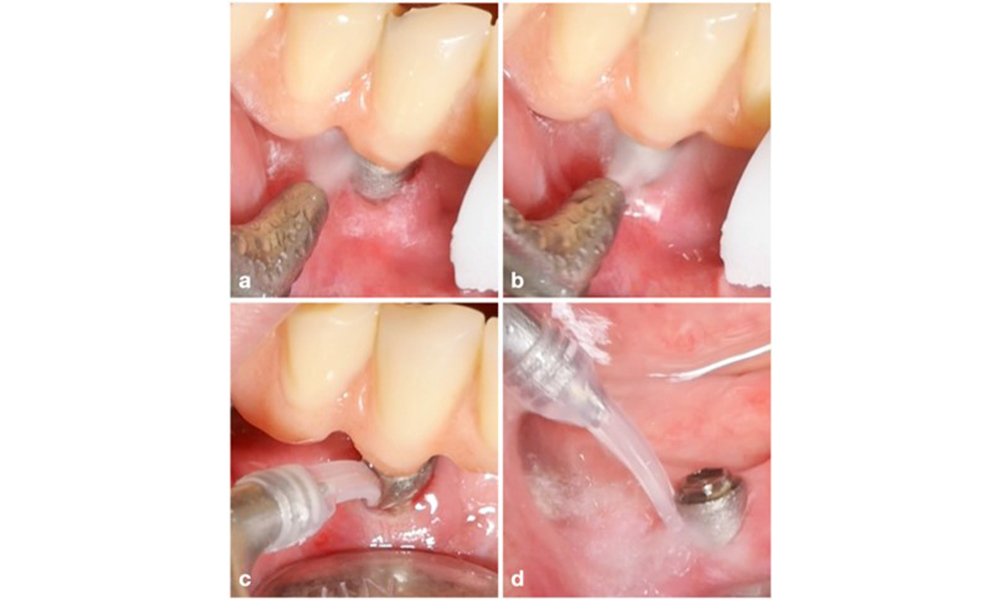

La prise en charge de la péri-implantite sur les implants jugés traitables consiste en une phase non chirurgicale, qui est souvent suivie d'une intervention chirurgicale. Pour l'approche non chirurgicale, des mesures similaires à celles appliquées pour le traitement de la mucosite péri-implantaire sont utilisées ; sur la base d'expériences de laboratoire, les dispositifs d'aéropolissage avec une buse sous-gingivale semblent offrir certains avantages en termes d'élimination du biofilm, par rapport aux instruments manuels ou à ultrasons (Herrera et al. 2023 ; Moharrami et al. 2019 ; Ronay et al. 2017) (figure 9).

Cas d'un patient souffrant de péri-implantite. Le traitement non chirurgical est réalisé à l'aide de la pièce à main supra-gingivale (a-b) et sous-gingivale d'un appareil d'aéro-polissage (c-d). Le retrait de la supra-construction permet un meilleur accès à la surface de l'implant (d).

Figure 9. Cas d'un patient souffrant de péri-implantite. Le traitement non chirurgical est réalisé à l'aide de la pièce à main supra-gingivale (a-b) et sous-gingivale d'un appareil d'aéro-polissage (c-d). Le retrait de la supra-construction permet un meilleur accès à la surface de l'implant (d).

Pourtant, l'approche non chirurgicale est souvent limitée dans l'accès à la surface de l'implant, ce qui conduit à une décontamination insuffisante. Cela se reflète en effet dans la clinique, où la résolution de la maladie après un traitement non chirurgical de la péri-implantite est plutôt imprévisible et la récurrence est observée dans la plupart des cas, c'est-à-dire que la résolution de la maladie n'a été signalée que dans moins d'un cas sur deux (Ramanauskaite et al. 2021). Par conséquent, le résultat du traitement non chirurgical doit être évalué après environ 6 semaines, et dans les cas de péri-implantite modérée ou avancée, il faut s'attendre à une intervention chirurgicale.